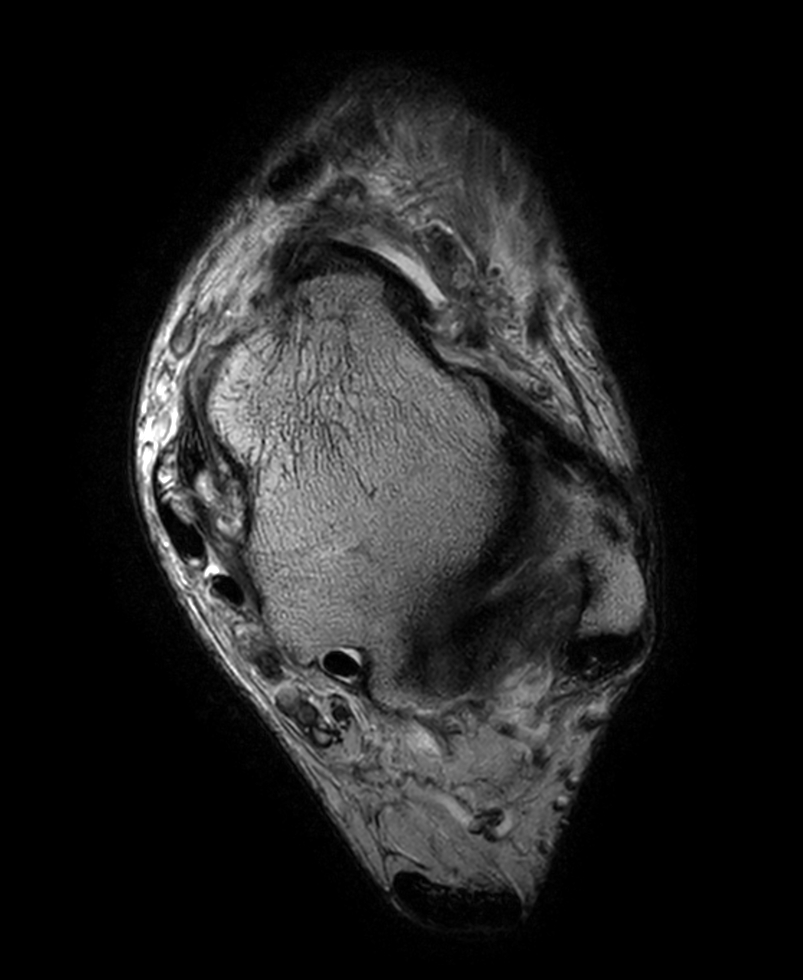

Axial 3D PDw MSK VIEW